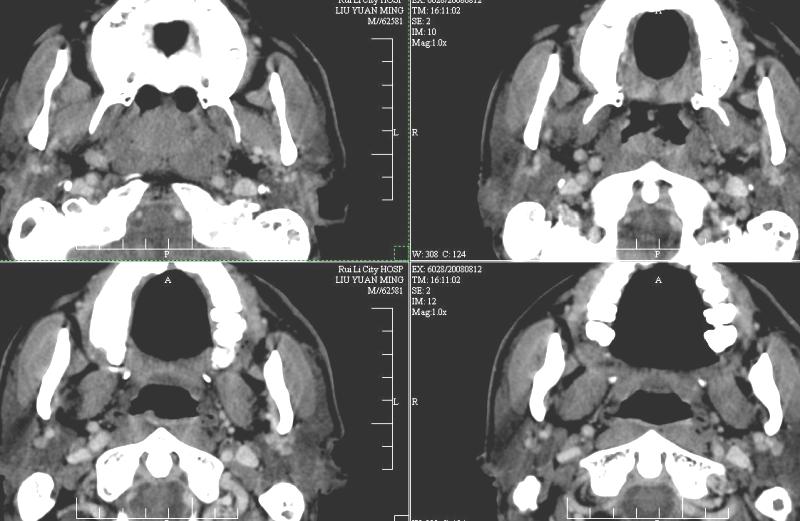

以下是引用ydx_74在2008-8-12 22:09:00的发言:[br]不考虑鼻咽癌。没有淋巴结肿大,没有颅底骨质破坏,咽隐窝、咽鼓管咽口存在,咽旁间隙清楚,平扫ct值34hu,增强动脉期81hu,实质期约85hu,增强幅度达50多,除外增强时机没有掌握好因素,可以考虑鼻咽纤维血管瘤吗?